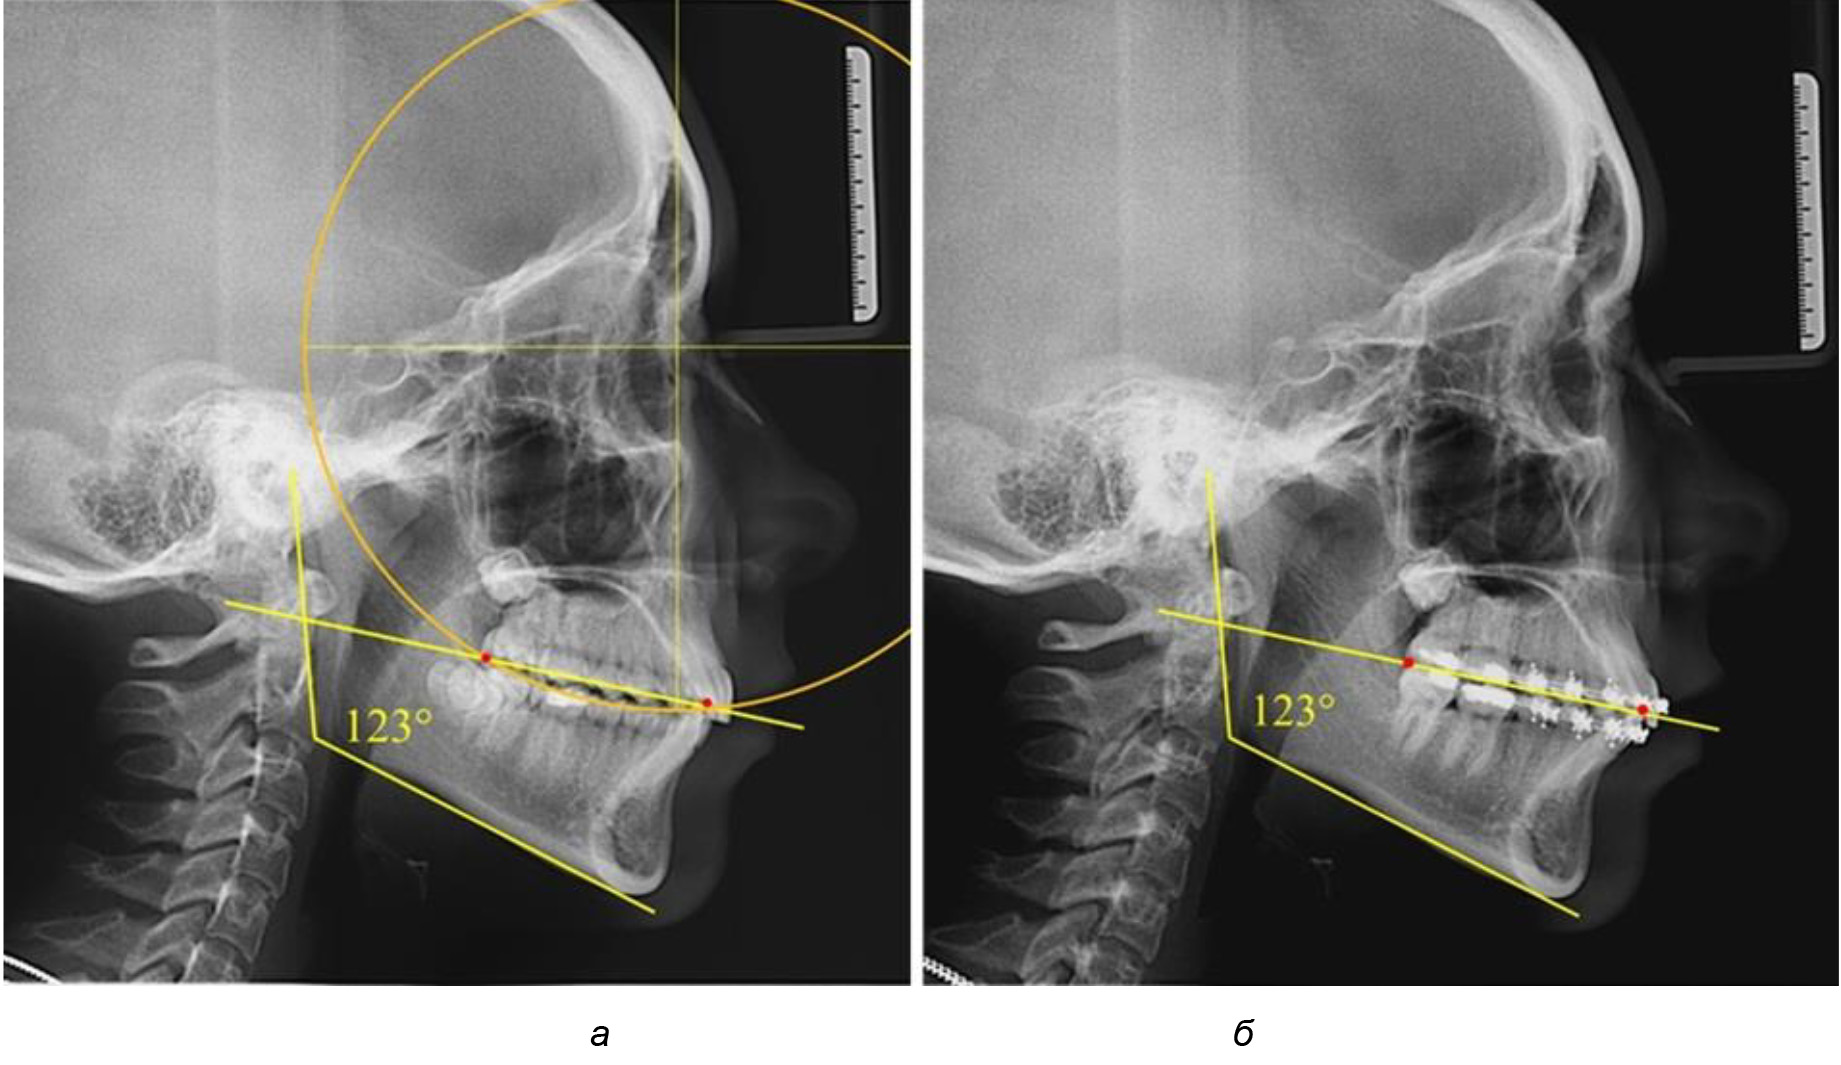

Деление величины радиуса круга к длине окклюзионной линии составило 1,623 ± 0,02. Таким образом, для определения радиуса окружности, соответствующей кривизне окклюзионного контура боковой ТРГ, необходимо измерить расстояние между передней и задней окклюзионными точками и последующим умножением полученной величины на число Фибоначчи (рис. 2).

Рис. 2. Особенности кривой Spee на ТРГ (а) и ОПТГ (б) у людей с признаками вертикального роста

На рентгенограммах людей 2-й подгруппы (30 человек с нейтральным типом роста) величина угла нижней челюсти в среднем составила (120,34 ± 2,19) ° и характеризовала нейтральный тип нижней челюсти.

Глубина кривой Spee в среднем по 2-й подгруппе составил (3,54 ± 0,58) мм, что было незначительно меньше, чем при анализе аналогичного показателя 1-й подгруппы.

Достоверных различий с показателями, полученными при анализе ТРГ и ОПТГ, нами не отмечено (р ˃ 0,05). Деление величины радиуса круга к длине окклюзионной линии составило 1,612 ± 0,02, что, так же как и в 1-й подгруппе, было близким по значению к числу Фибоначчи (1, 618).